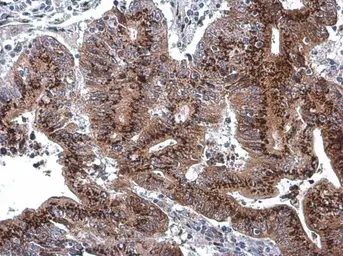

GOLPH2 antibody [C3], C-term detects GOLPH2 protein at cytoplasm by immunohistochemical analysis.

Sample: Paraffin-embedded human colon cancer.

GOLPH2 stained by GOLPH2 antibody [C3], C-term (GTX107702) diluted at 1:1000.

Antigen Retrieval: Citrate buffer, pH 6.0, 15 min